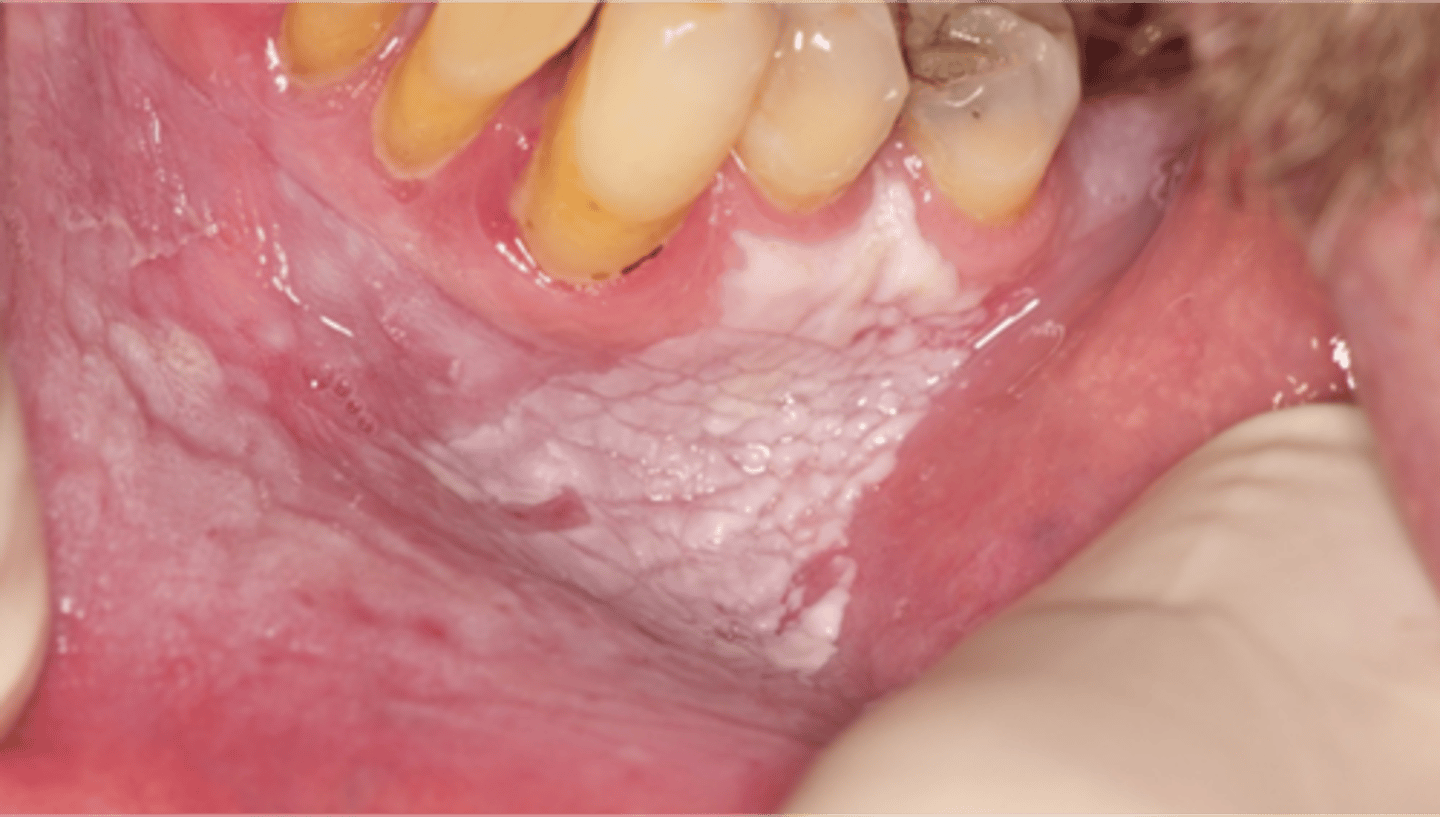

What is proliferative verrucous leukoplakia? (+ % malignant transformation, population)

⢠extensive, multiple white corrugated plaques

⢠NOT associated with risk factors -- 70% malignant change

⢠must biopsy

⢠Population: females over 50